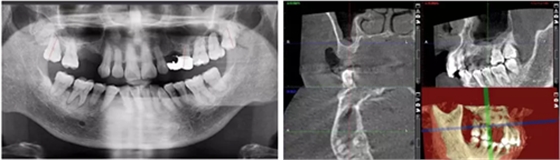

術后當天 術后7個月